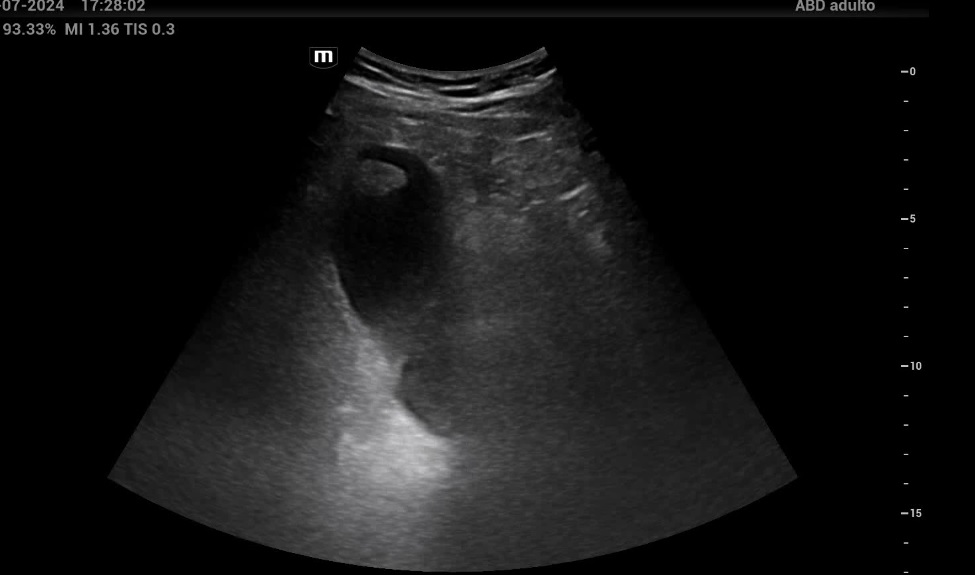

En la ecografía clínica, la vesícula biliar presentaba imagen ecogénica de bordes bien definidos, sin sombra acústica posterior, localizada en cúpula vesicular. Se pidió al paciente que se colocara en decúbito lateral izquierdo y se comprobó que la lesión continuaba localizada en cúpula vesicular, sin haberse desplazado al movilizar al paciente. Dicha lesión presentaba un tamaño de 2,8 x 1,7 cm (imagen 28), y se activó Doppler, observándose que dicha lesión tenía una captación central de Doppler, correspondiente a un vaso nutricio. La pared de la vesícula no estaba engrosada y no había dilatación de vía biliar intra ni extrahepática.

El diagnóstico fue de pólipo vesicular. Dentro del diagnóstico diferencial tenemos que pensar en un cólico biliar, una colecistitis, una coledocolitiasis o una colangitis. En pacientes con episodios repetidos de dolor en hipocondrio derecho, con la ecografía podemos descartar que se trate de colelitiasis al observar cálculos en su interior. Si el paciente asocia fiebre, la ecografía nos ayudará con el diagnóstico de colecistitis (presencia de colelitiasis, vesícula distendida, y pared engrosada). Como en este caso, podemos encontrar patología menos prevalente y que se diferencia de las litiasis por no presentar sombra acústica posterior, por no ser móviles y porque en ocasiones pueden presentar captación Doppler.